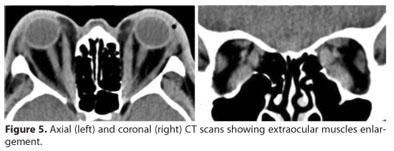

A 60-year-old white man with Graves' disease and a 15-day history of bilateral globe subluxation was referred by a general ophthalmologist. Similar to case 1, the patient had been previously treated with anti-thyroid drugs, beta-blockers, and oral and intravenous steroid pulse therapy without improvement. On examination, both eyes were subluxated with marked chemosis and congestion and virtually no ocular motility (Figure 4). Visual acuity was hand motion in the right eye and light perception in the left. The left cornea was melting. Globe protrusion was estimated with a ruler to be around 40 mm in both eyes. Orbital CT scans demonstrated bilateral enlargement of the inferior and medial recti (Figure 5). He was admitted to the hospital and first underwent urgent temporary transverse blepharotomy and temporary tarsorraphy. The next day a bilateral three-wall orbital decompression was performed by a coronal approach.

Our cases were completely different. The two patients reported here and the third one reported in Israel were all in the active phase of the disease. Orbital CT scans showed marked EOM enlargement and severely impaired eye motility. The mechanisms of globe subluxation in these patients thus differ from those of previously reported cases. We believe that intense orbital inflammation associated with marked upper eyelid retraction due to levator muscle infiltration is capable to displace the eyeball even in the presence of rectus enlargement. In our cases the upper eyelids were fixed in a high position and globe repositioning was impossible without surgery.